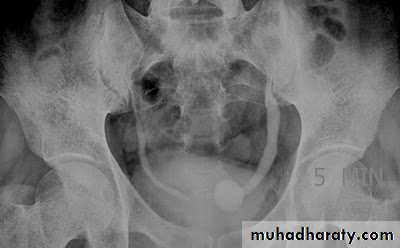

Ectopia vesica :

bladder located at low position & plain x-ray shows separation of symphysis pubis .